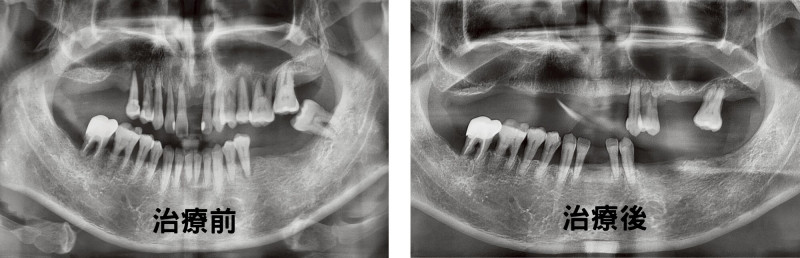

吳欣哲以牙周探針、X光檢查該市民,發現牙齒搖度高,懷疑代謝系統異常而轉診,發現他飯後血糖遠高於標準值200mg/dL,吳欣哲說明,血糖控制不佳會讓牙周病機率提升2倍到3倍,加上有抽菸習慣更會風險拉升到4.6倍,後續安排該市民同步接受糖尿病、牙周病治療後,順利保住他的11顆牙,並於牙周病療程結束後進行假牙重建,恢復他的正常咀嚼功能。

該市民後續定期回診接受支持性治療,經5年追蹤,糖化血色素控制在7%以下、11顆牙狀況良好。吳欣哲說,牙周病治療結束後的支持性治療,是防範復發的關鍵,須定期回診才能徹底清除累積的結石與牙菌斑;牙周病患者完成基礎治療或手術後,若自覺症狀改善而忽略支持性治療,牙周病極有可能全面復發,甚至曾有患者7年後齒槽骨損毀程度更勝以往,結果只能拔牙與進行重建手術救治。